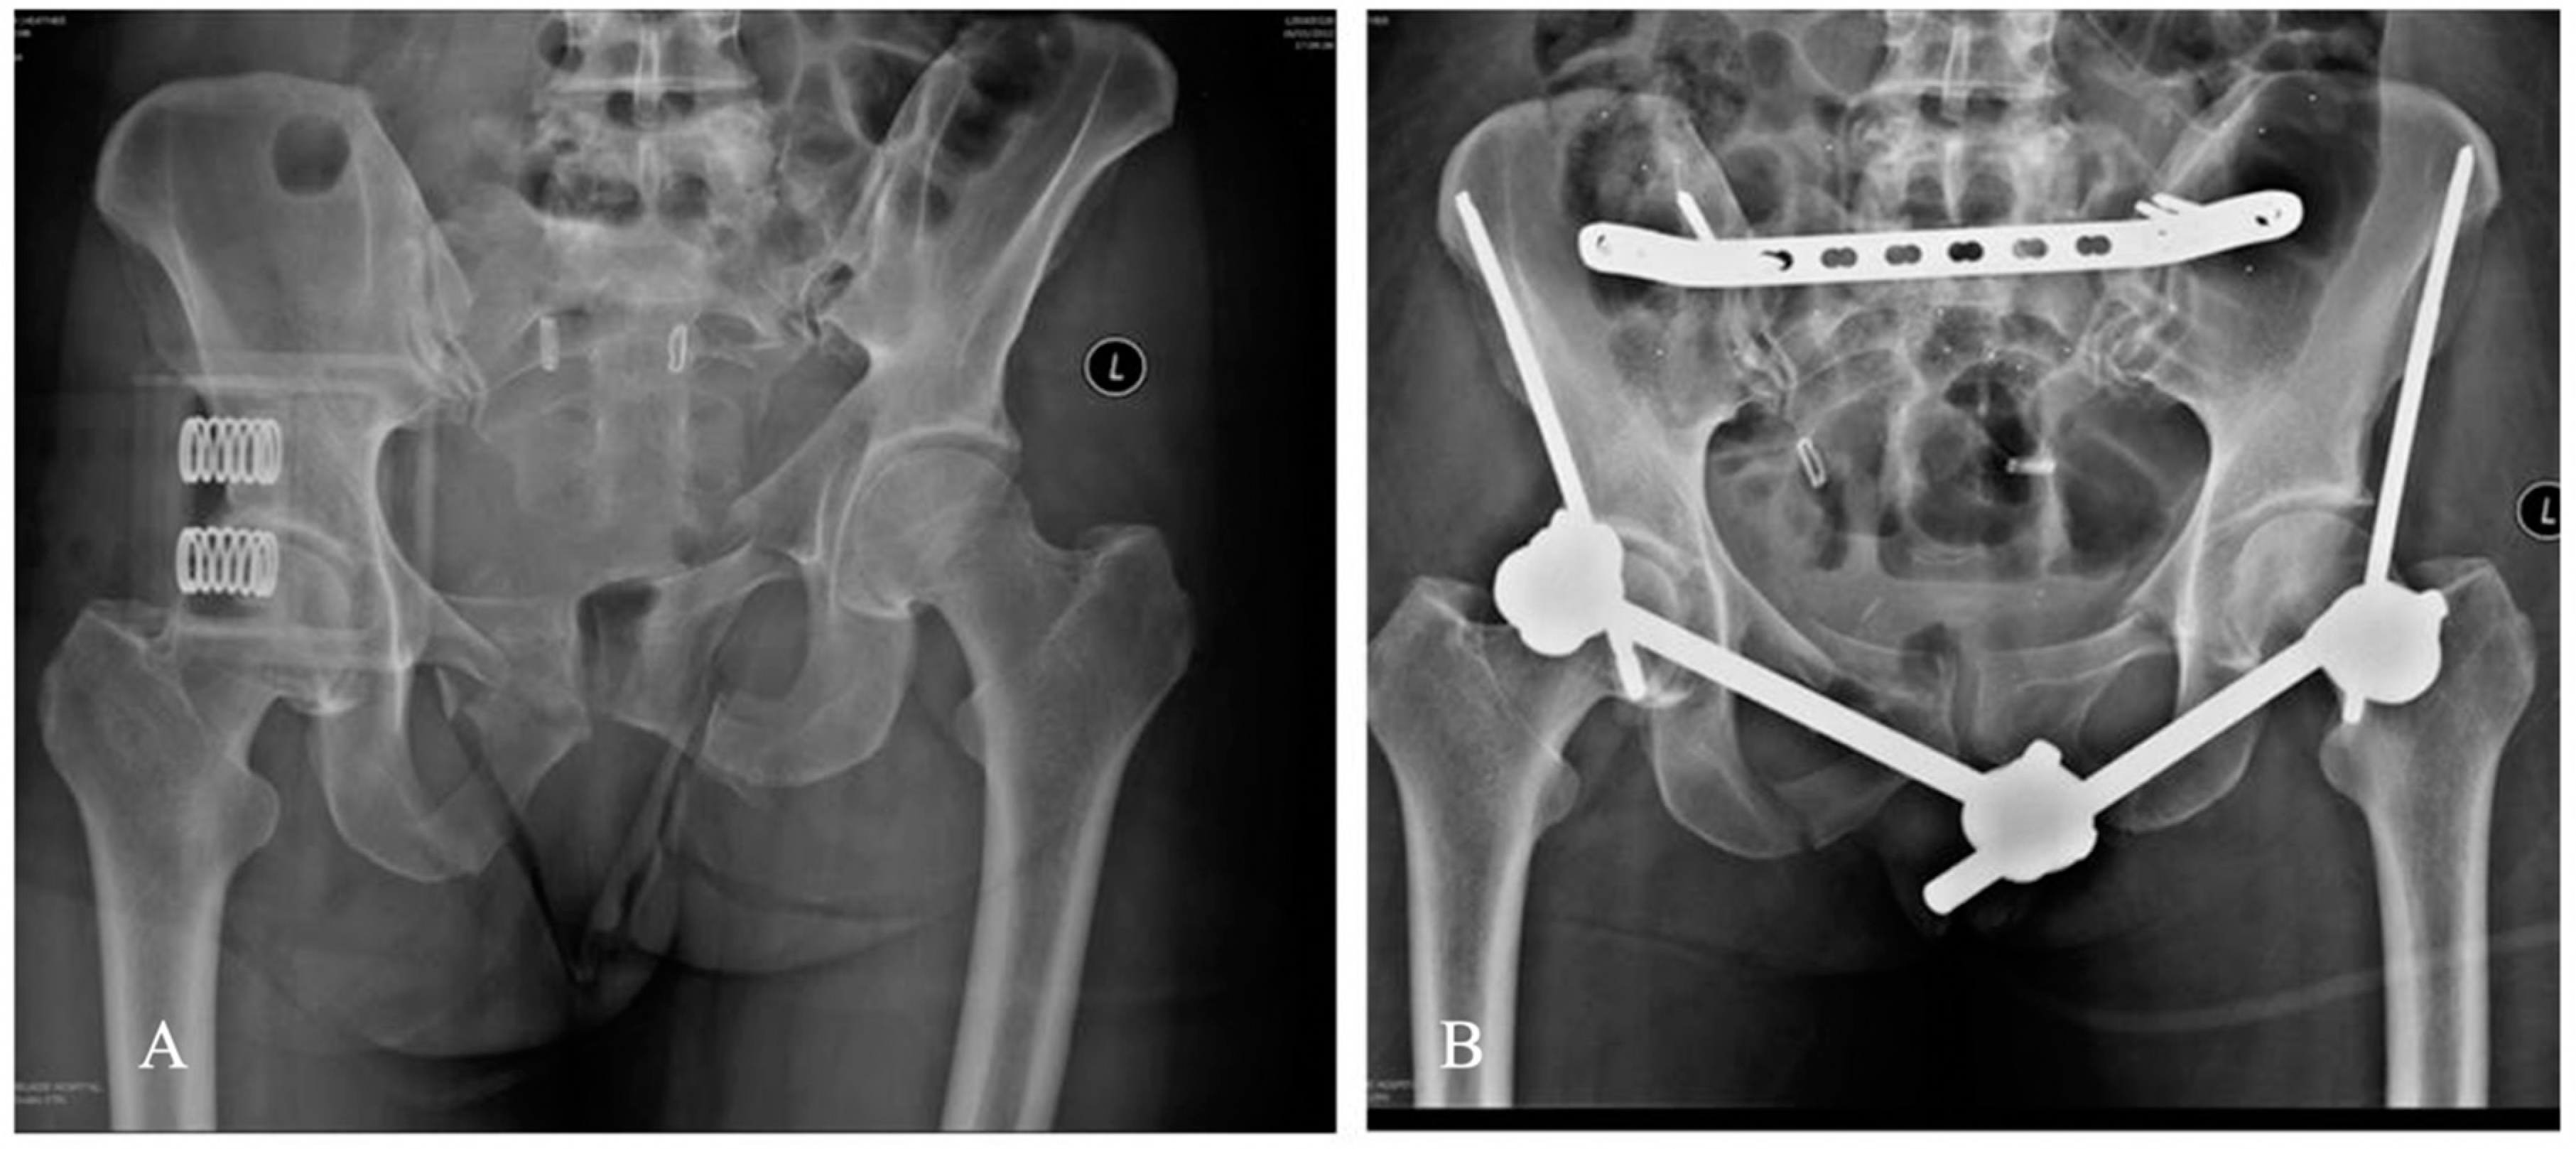

3.3. Radiographic Results

3.4. RSA